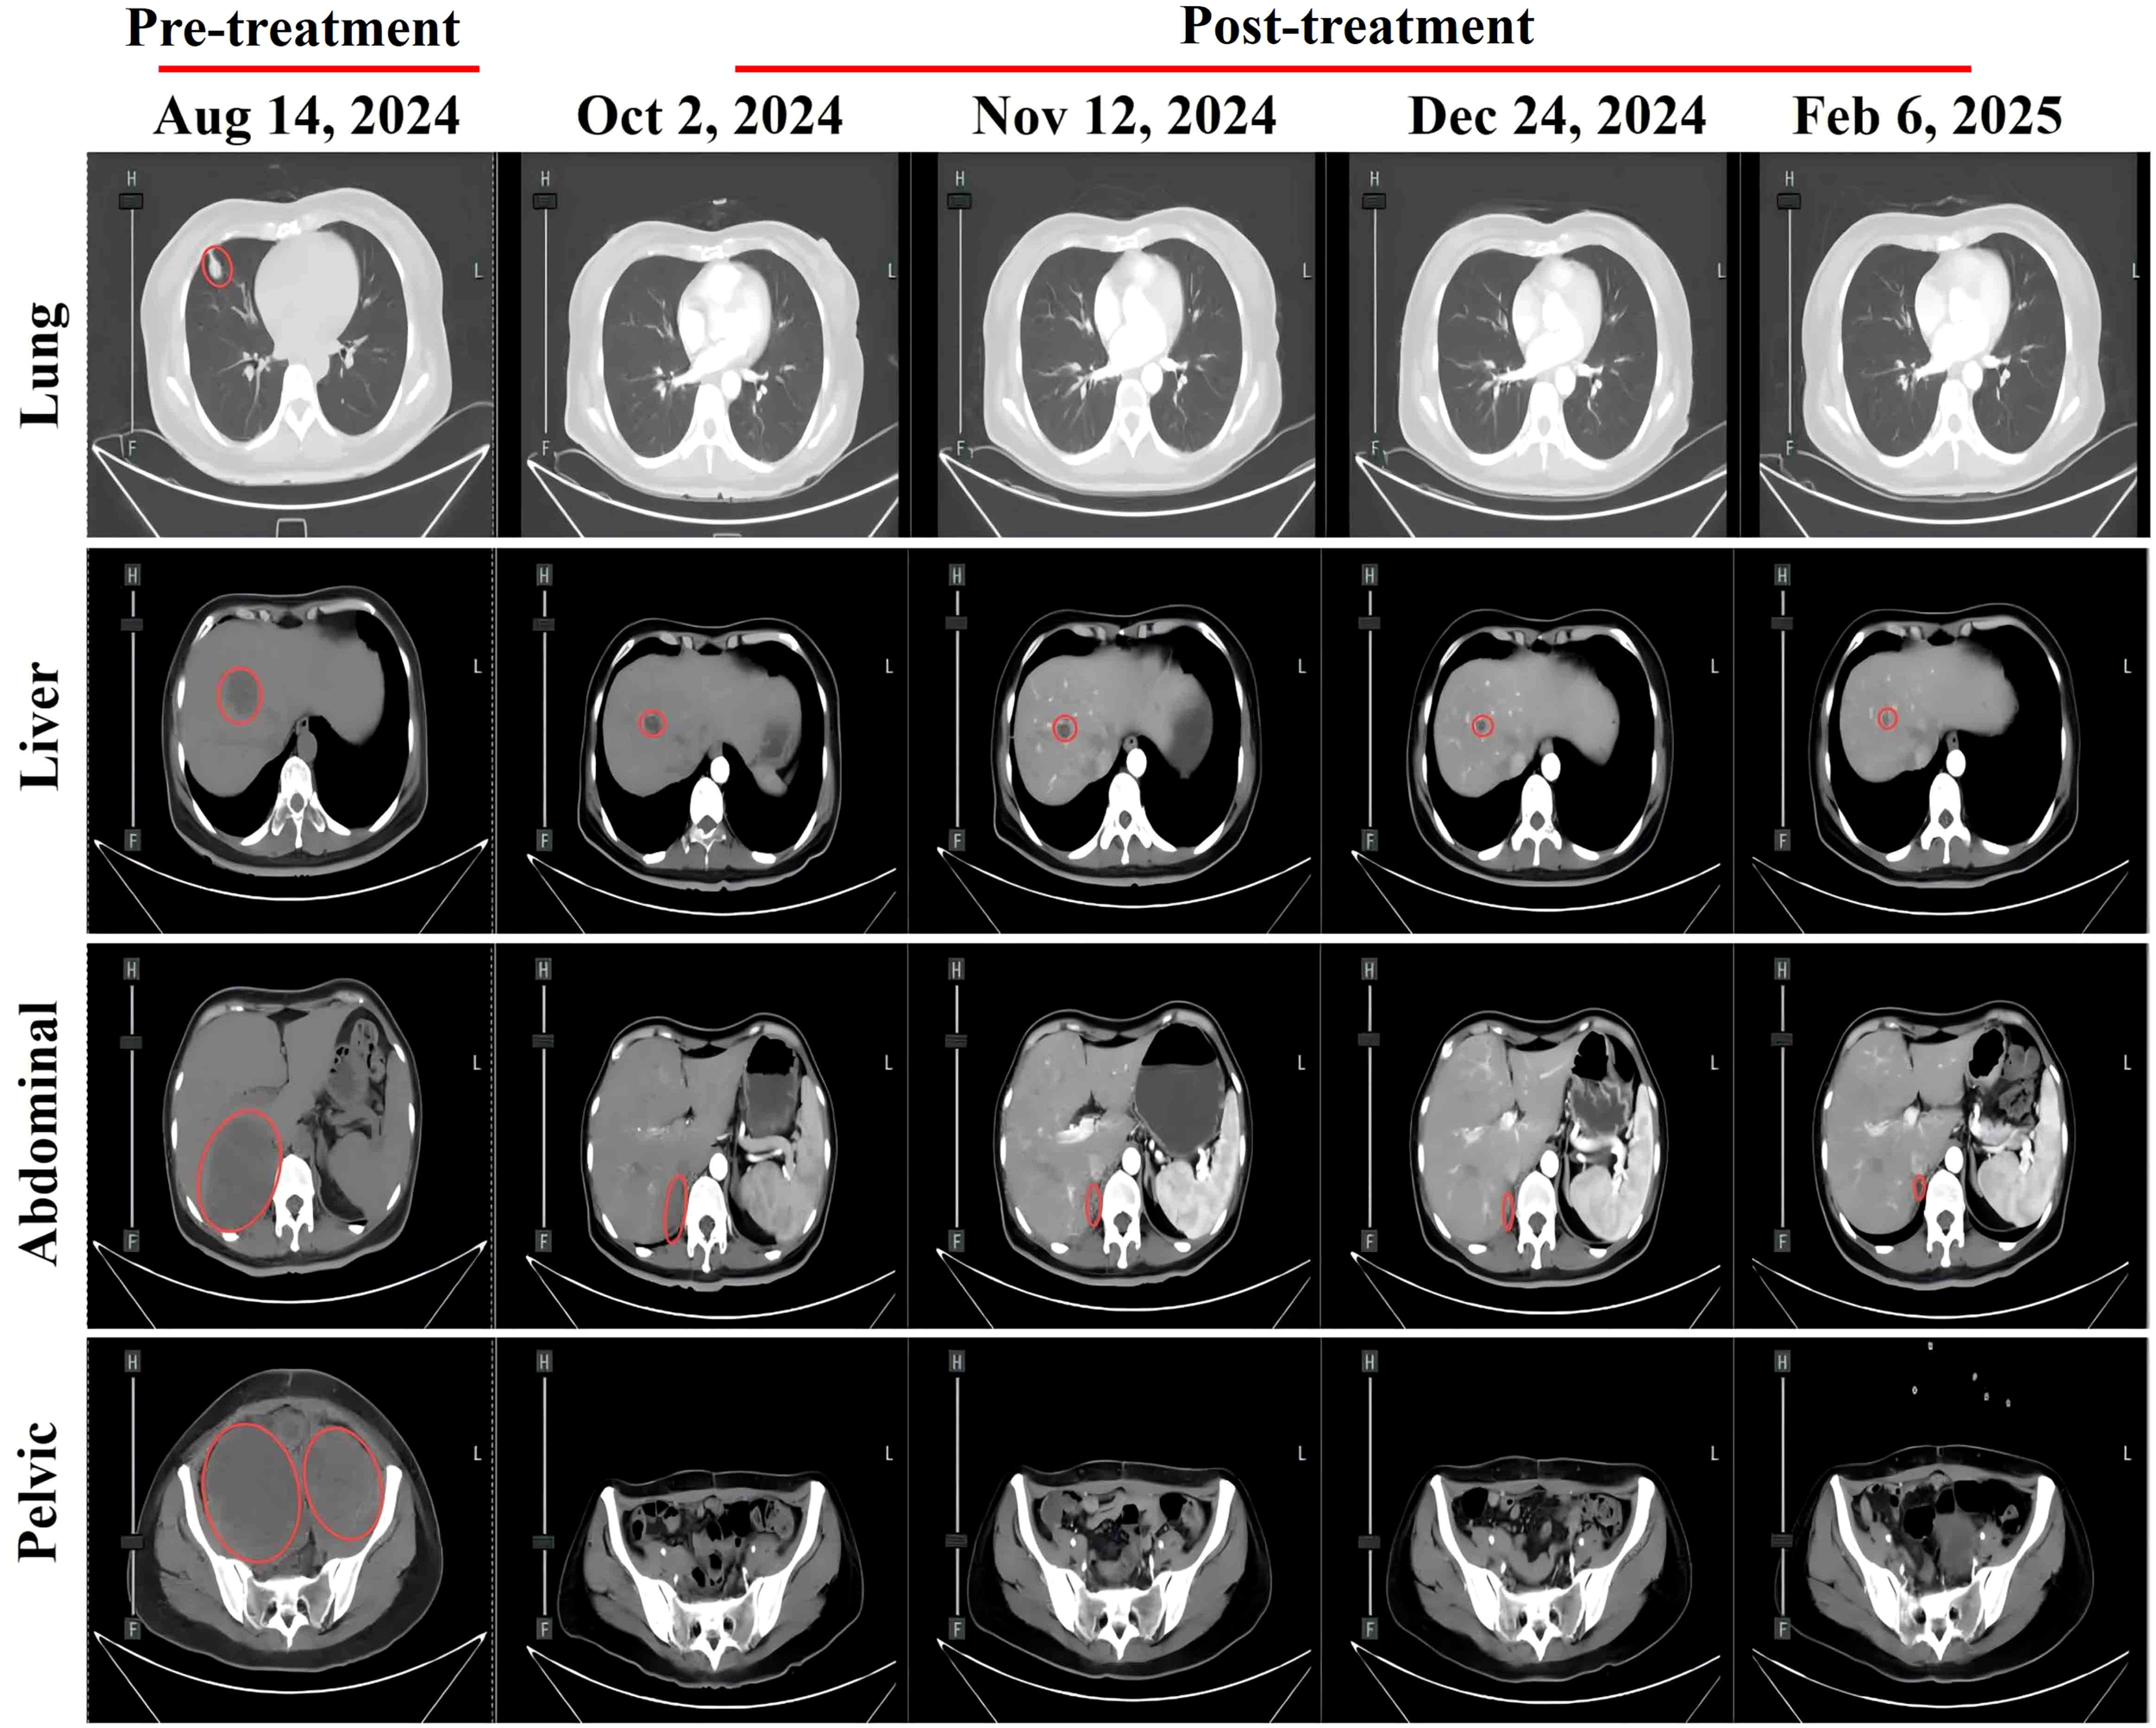

Figure 3

Abdominal CT scans at different treatment time points showing changes in metastatic lesions: pulmonary metastasis, hepatic metastasis, abdominal metastasis, and pelvic metastasis. Red circles indicate metastatic lesions.

The patient developed acute renal failure due to tumor progression and was recommended for nephrostomy to relieve obstruction, followed by antitumor treatment. On August 16, 2024, bilateral nephrostomy was performed under local anesthesia, and kidney function gradually improved thereafter. Next-generation sequencing revealed no detectable mutations in MET, KRAS, NRAS, ROS1, BRAF, or KIT. However, the tumor harbored both high-level ERBB2 (HER2) amplification, with an estimated copy number of 74.5, and a pathogenic ERBB2 point mutation (c.2264T>C, p.L755S, exon 19), detected at a high variant allele frequency of 98.36%. Given the patient’s acute renal injury and elevated creatinine levels, traditional chemotherapy was considered unsuitable due to compromised renal function. Genetic testing revealed the presence of HER2 co-alteration, including both HER2 amplification and a HER2 point mutation, suggesting potential sensitivity to HER2-targeted therapy. Therefore, the patient was administered an exploratory treatment regimen consisting of T-DXd (200 mg on Day 1) and toripalimab (240 mg on Day 1), for a total of nine treatment cycles. (Figure 2). Imaging assessments (chest and abdominal CT scans) were performed at approximately six-week intervals during the treatment period, specifically on October 2, 2024; November 12, 2024; December 24, 2024; and February 6, 2025. On September 11, 2024, following two cycles (approximately six weeks), a partial response (PR) was observed, with significant tumor shrinkage as assessed by the Response Evaluation Criteria in Solid Tumors (RECIST) guidelines. Subsequent evaluations on October 23, 2024, December 4, 2024, and January 16, 2025, showed stable disease (SD), with no progression but no further significant shrinkage of the tumors (Figure 3). As of February 7, 2025, the patient continues maintenance therapy with the same regimen and is being closely monitored for further disease progression. During the treatment period, complete blood count and liver function tests were monitored every three weeks. The patient tolerated the treatment well, with no significant adverse reactions observed.